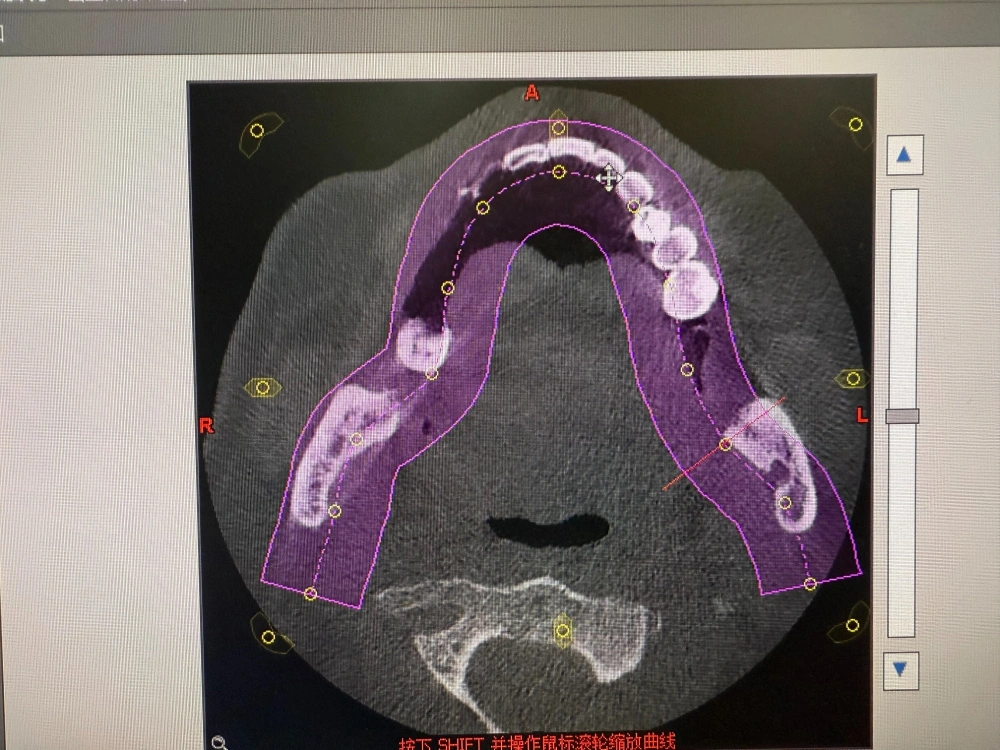

我是当事人的女儿,我父亲今年77岁了,事发前他刚从海南回东北跟我们子女在一起聚聚,他当时有四颗坏掉的牙想尽快根治。7月16日,他看到了哈尔滨市优诺口腔的宣传小广告后一个人去医院咨询,本来想治牙,结果医院建议我父亲把下部的牙全部拔掉后种牙,还说种完牙后吃麻麻香,但现在从片子上来看完全没必要这样做。事发后我们询问了其他口腔医院的医生,所有的医生都说拔牙要评估病人的身体,以我爸高血压、糖尿病、冠心病还有5个心脏支架这种情况,他们可能连拔牙都不会,更不用说一次性拔12颗,甚至还种了6颗,这个破坏是非常大的,正常人可能都受不了,全国都没有这样的案例。